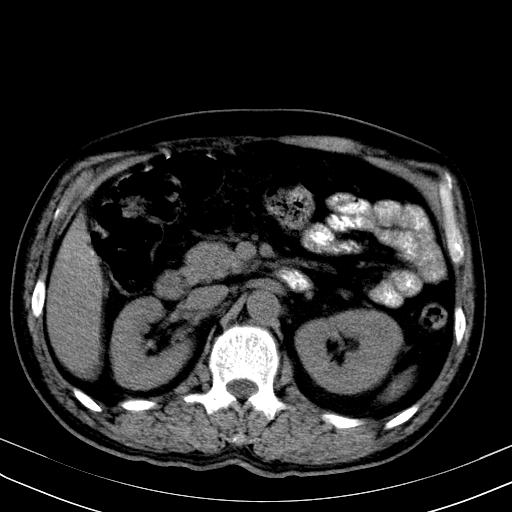

先行ct平扫,纵膈内多发软组织影,ct值约为36hu,以下为增强扫描和腹部平扫。

经典?纵膈多发肿大淋巴结。腹膜后未见异常。

还见胃窦壁增厚!转移亦有可能!

大家看看肝脏右叶片状低密度影是什么改变啊?

淋巴瘤?肝脏请增强后说啊

多发肿大淋巴结影,肝内改变需结合强化观察